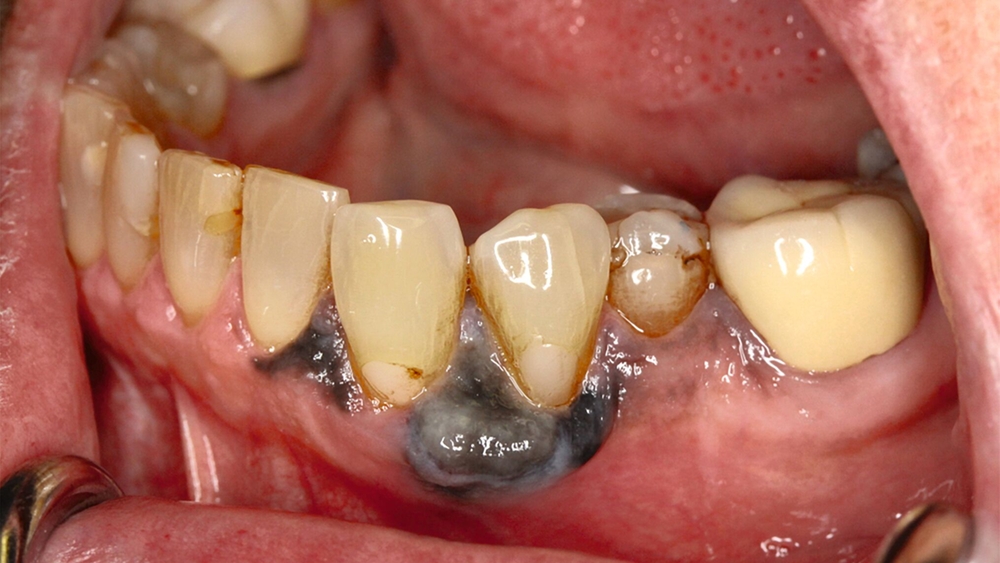

Eine im Januar 2024 alio loco durchgeführte Probenentnahme ergab eine resorptive Entzündung mit Pigmenteinlagerungen. Die Patientin berichtet, dass die Schleimhautveränderung etwa vier Wochen vor der Vorstellung bei uns begonnen habe zu wuchern. Klinisch zeigte sich eine 10 mm x 7 mm messende, exophytisch wachsende, schwarz pigmentierte Raumforderung (Abbildungen 1 und 2). Durch eine Probenentnahme in domo konnte histopathologisch ein malignes Melanom gesichert werden.

Differenzialdiagnostisch muss an Amalgamtätowierungen, ethnienspezifische Pigmentierungen oder orale Naevi gedacht werden, aber auch internistische Erkrankungen wie Morbus Addison oder genetische Syndrome wie das Peutz-Jeghers-Syndrom können orale Pigmentierungen verursachen [Abati et al., 2024].